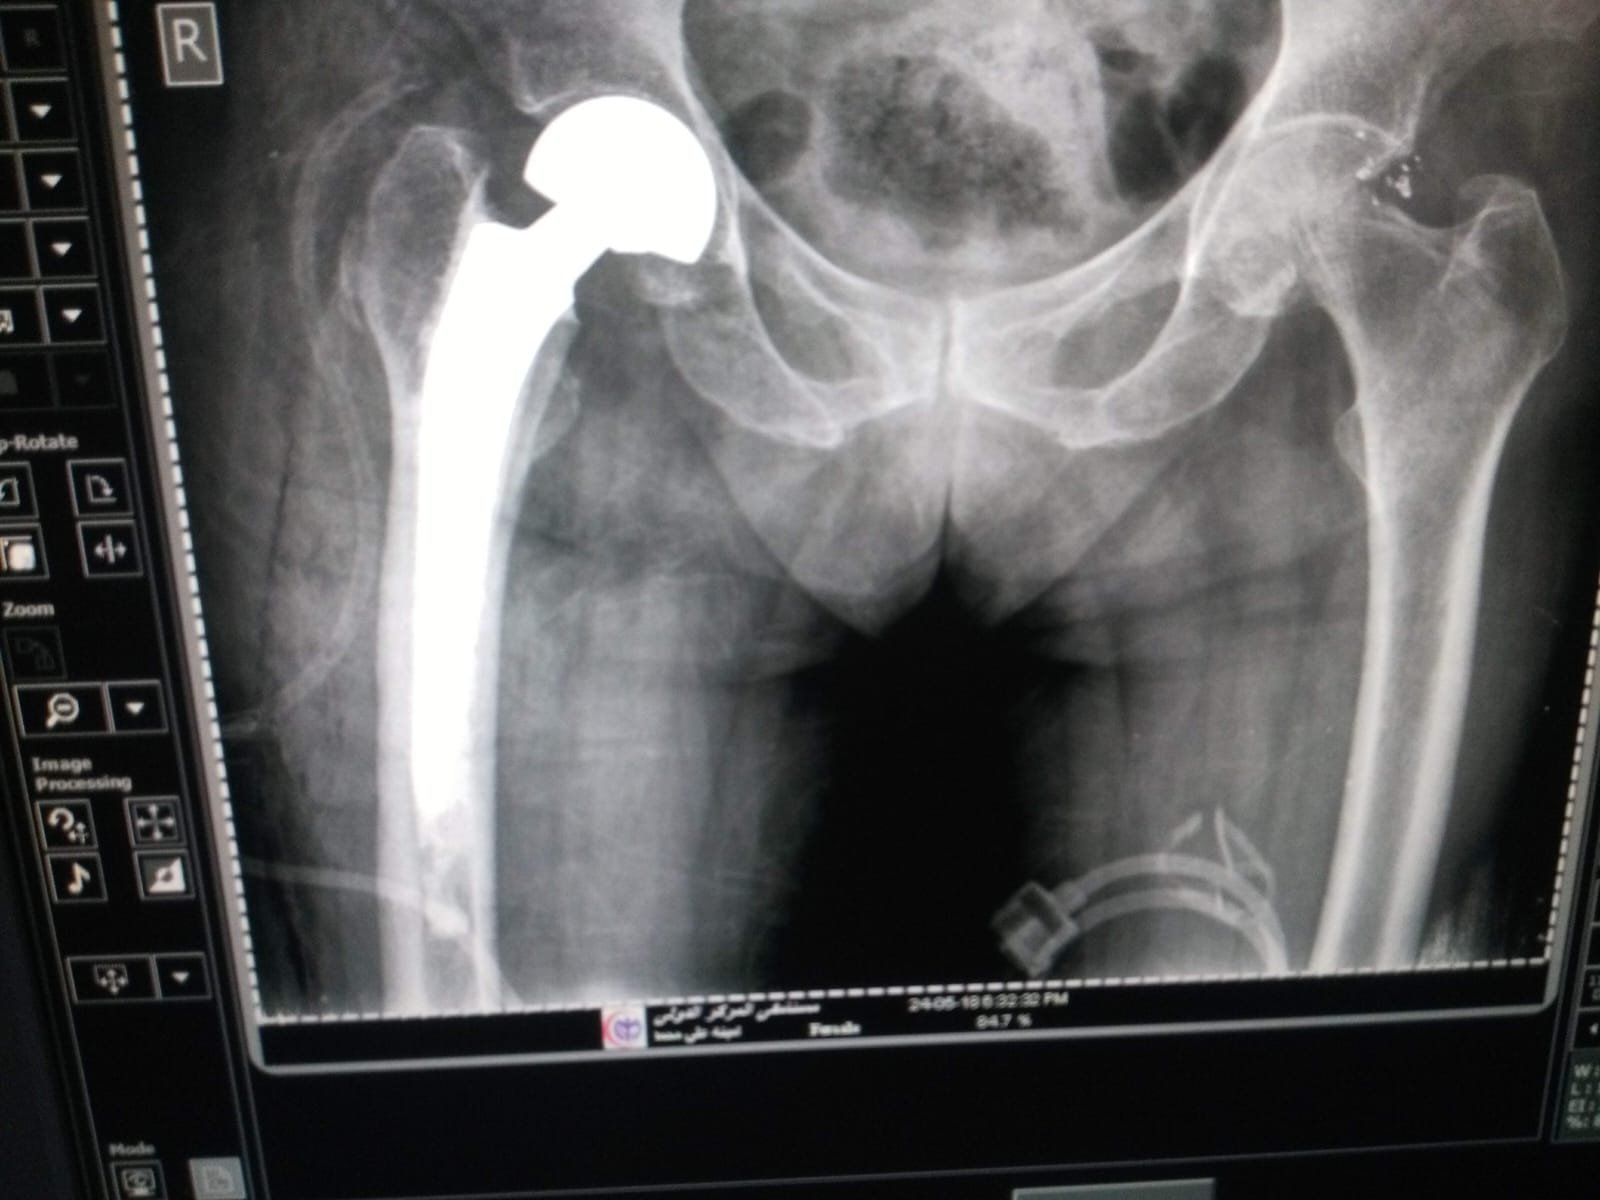

بناءً على خبرة د. أحمد نبيل عمارة في جراحة العظام والمفاصل والمناظير، يبدأ بتشخيص دقيق يحدّد درجة الخشونة وخطة العلاج الأنسب؛ من العلاج التحفّظي الدوائي والحقن الموجّهة (PRP/HA/كورتيزون) إلى المناظير والجراحات عند الحاجة، بهدف تقليل الألم واستعادة الحركة بأمان.